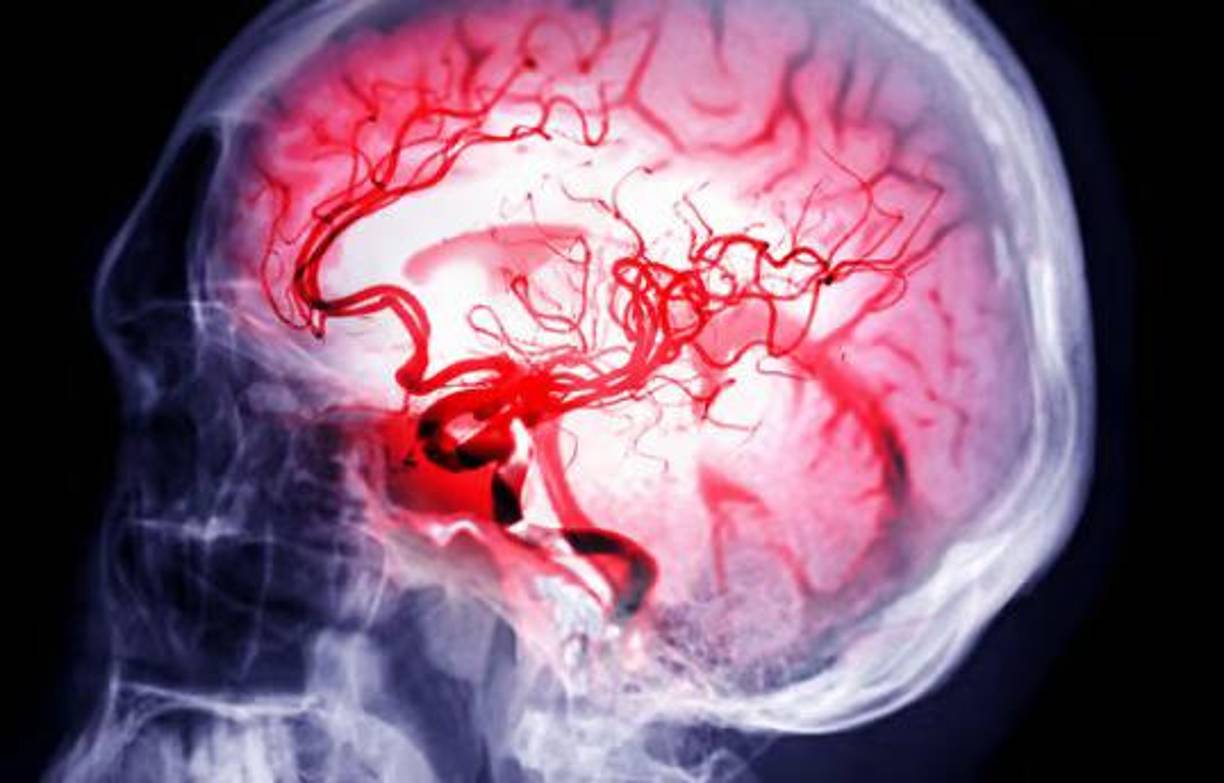

13 / 14Un accidente cerebrovascular hemorrágico ocurre cuando un vaso sanguíneo de una parte del cerebro se debilita y se rompe. Esto provoca que la sangre se escape hacia el cerebro. Algunas personas tienen defectos en los vasos sanguíneos del cerebro que hacen que esto sea más probable. Estos defectos pueden incluir:

14 / 14- Aneurisma (un área débil en la pared de un vaso sanguíneo que provoca que al vaso se le forme una protuberancia o una burbuja en la parte exterior)

- Malformación arteriovenosa (MAV; una conexión anormal entre las arterias y venas)

- Angiopatía cerebral amiloide (ACA: una afección en la que las proteínas amiloides se acumulan en las paredes de las arterias del cerebro)